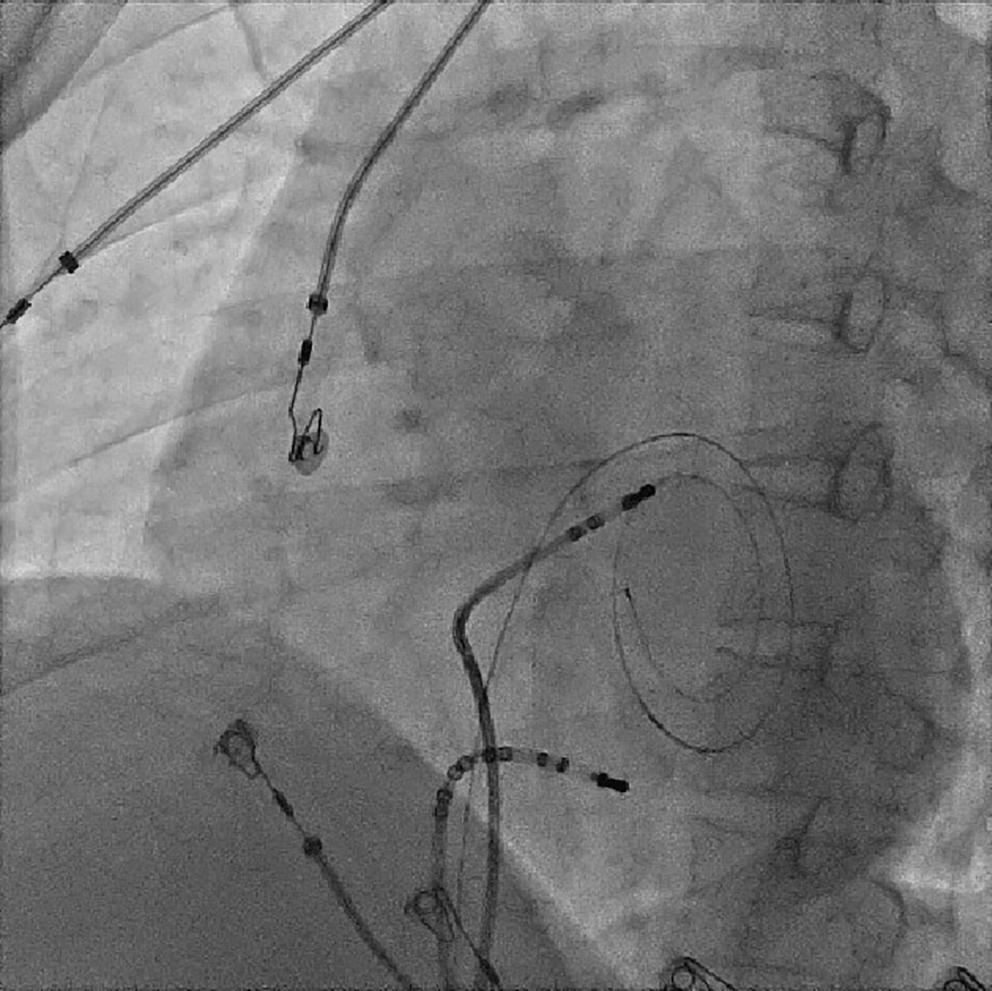

Because the patient had baseline pre-excitation through the right posterior septal path and atrial flutter with orthodromic conduction with right bundle branch aberration, one decapolar catheter in the coronary sinus and a quadripolar catheter in the right ventricle were used to study the effective refractory period (ERP) of the accessory pathway rather than using the routine four electrophysiology catheters (three quadripolar [high right atrial, His bundle, right ventricle apex] and one decapolar catheter in the coronary sinus; Figure 4C). The supra-His conduction time was 65 ms and the infra-His conduction time was 9 ms. The baseline ECG was suggestive of a right posterior septal pathway. Right ventricular pacing showed eccentric conduction up to 450 ms, which suggested a retrograde pathway ERP of 450 ms. On pacing the integrated pathway, the ERP was found to be 450 ms. Due to the weak nature of the accessory pathway, ablation was not performed. On rapid atrial pacing, atrial flutter with right bundle branch aberrancy was induced, similar to the clinical tachycardia observed earlier. Ablation for the atrial flutter was not performed, and the patient was maintained on metoprolol succinate and an oral anticoagulant

Figure 4: Electrophysiology Study to Map the Accessory Pathway

Figure 3: Transsepetal Puncture for Balloon Mitral Valvotomy and Electrophysiology Study in One Go A: Septal puncture using fluoroscopy and transesophageal echocardiography guidance. B: A 23–26 mm Accura balloon was inflated to 26 mm in the right anterior oblique view. Electrophysiological study using one quadripolar catheter for right ventricle pacing and one decapolar catheter in the coronary sinus.